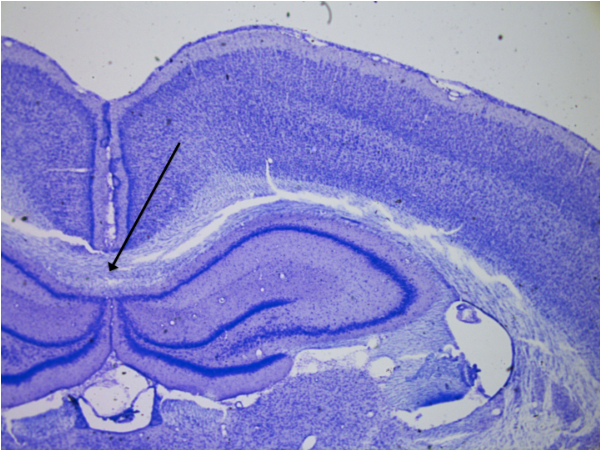

Cerebellum

knowt flashcard image